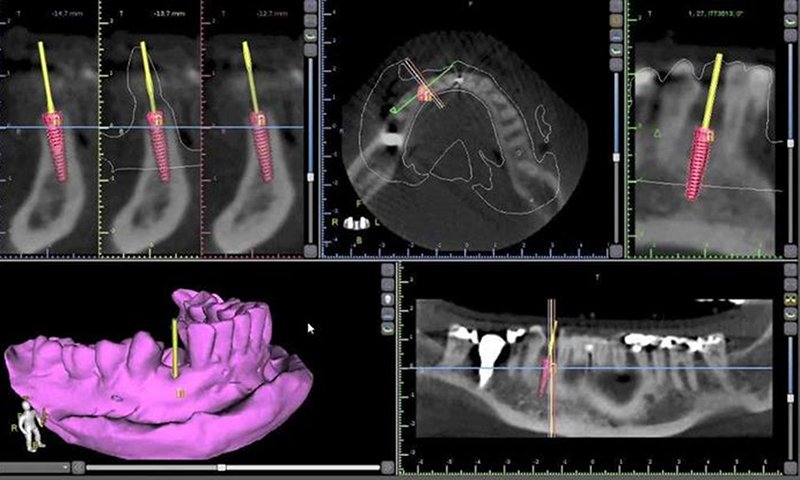

Conhecida como TC, gera imagens transversais (em "fatias") e de alta resolução, utilizando raios-X e processamento de computador. Essas fatias podem ser reconstruídas em 3D, permitindo uma visualização detalhada de qualquer ângulo.

O exame padrão-ouro para planejamento de implantes dentários é a Tomografia Computadorizada de Feixe Cônico (TCFC), também conhecida como tomografia odontológica 3D. Diferente de um raio-X simples, ela fornece imagens tridimensionais detalhadas, essenciais para a segurança do procedimento.